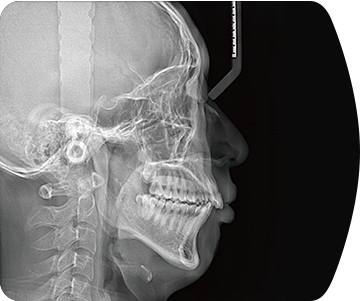

临床样片